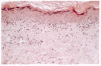

De los exámenes realizados destacaba una electroforesis de proteínas con hipoalbuminemia, leve aumento de alfa 2 y betaglobulinas y en zona de gamma una fracción de mayor concentración. La biopsia de piel de julio 1996 demostró atrofia epidérmica y regular infiltrado linfocitario en banda sub-epitelial con linfocitos en la unión dermoepidérmica, borramiento del límite dermoepidérmico, cuerpos coloideos y numerosos macrófagos cargados de pigmento; se informó como dermatitis liquenoidea (Fig. 2) y la electromiografia reveló compromiso miopático leve a moderado con neuroconducción normal, lo cual no era muy concordante con polimiositis, aunque tampoco la descartaba. Otros exámenes de ingreso fueron radiografía de tórax, hemograma y proteína C reactiva dentro de límites normales.

FIG. 2.--Infiltración linfocítica con borramiento de la unión dermoepidérmica.